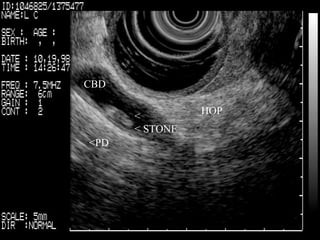

CBD   <  < STONE   <PD   HOP